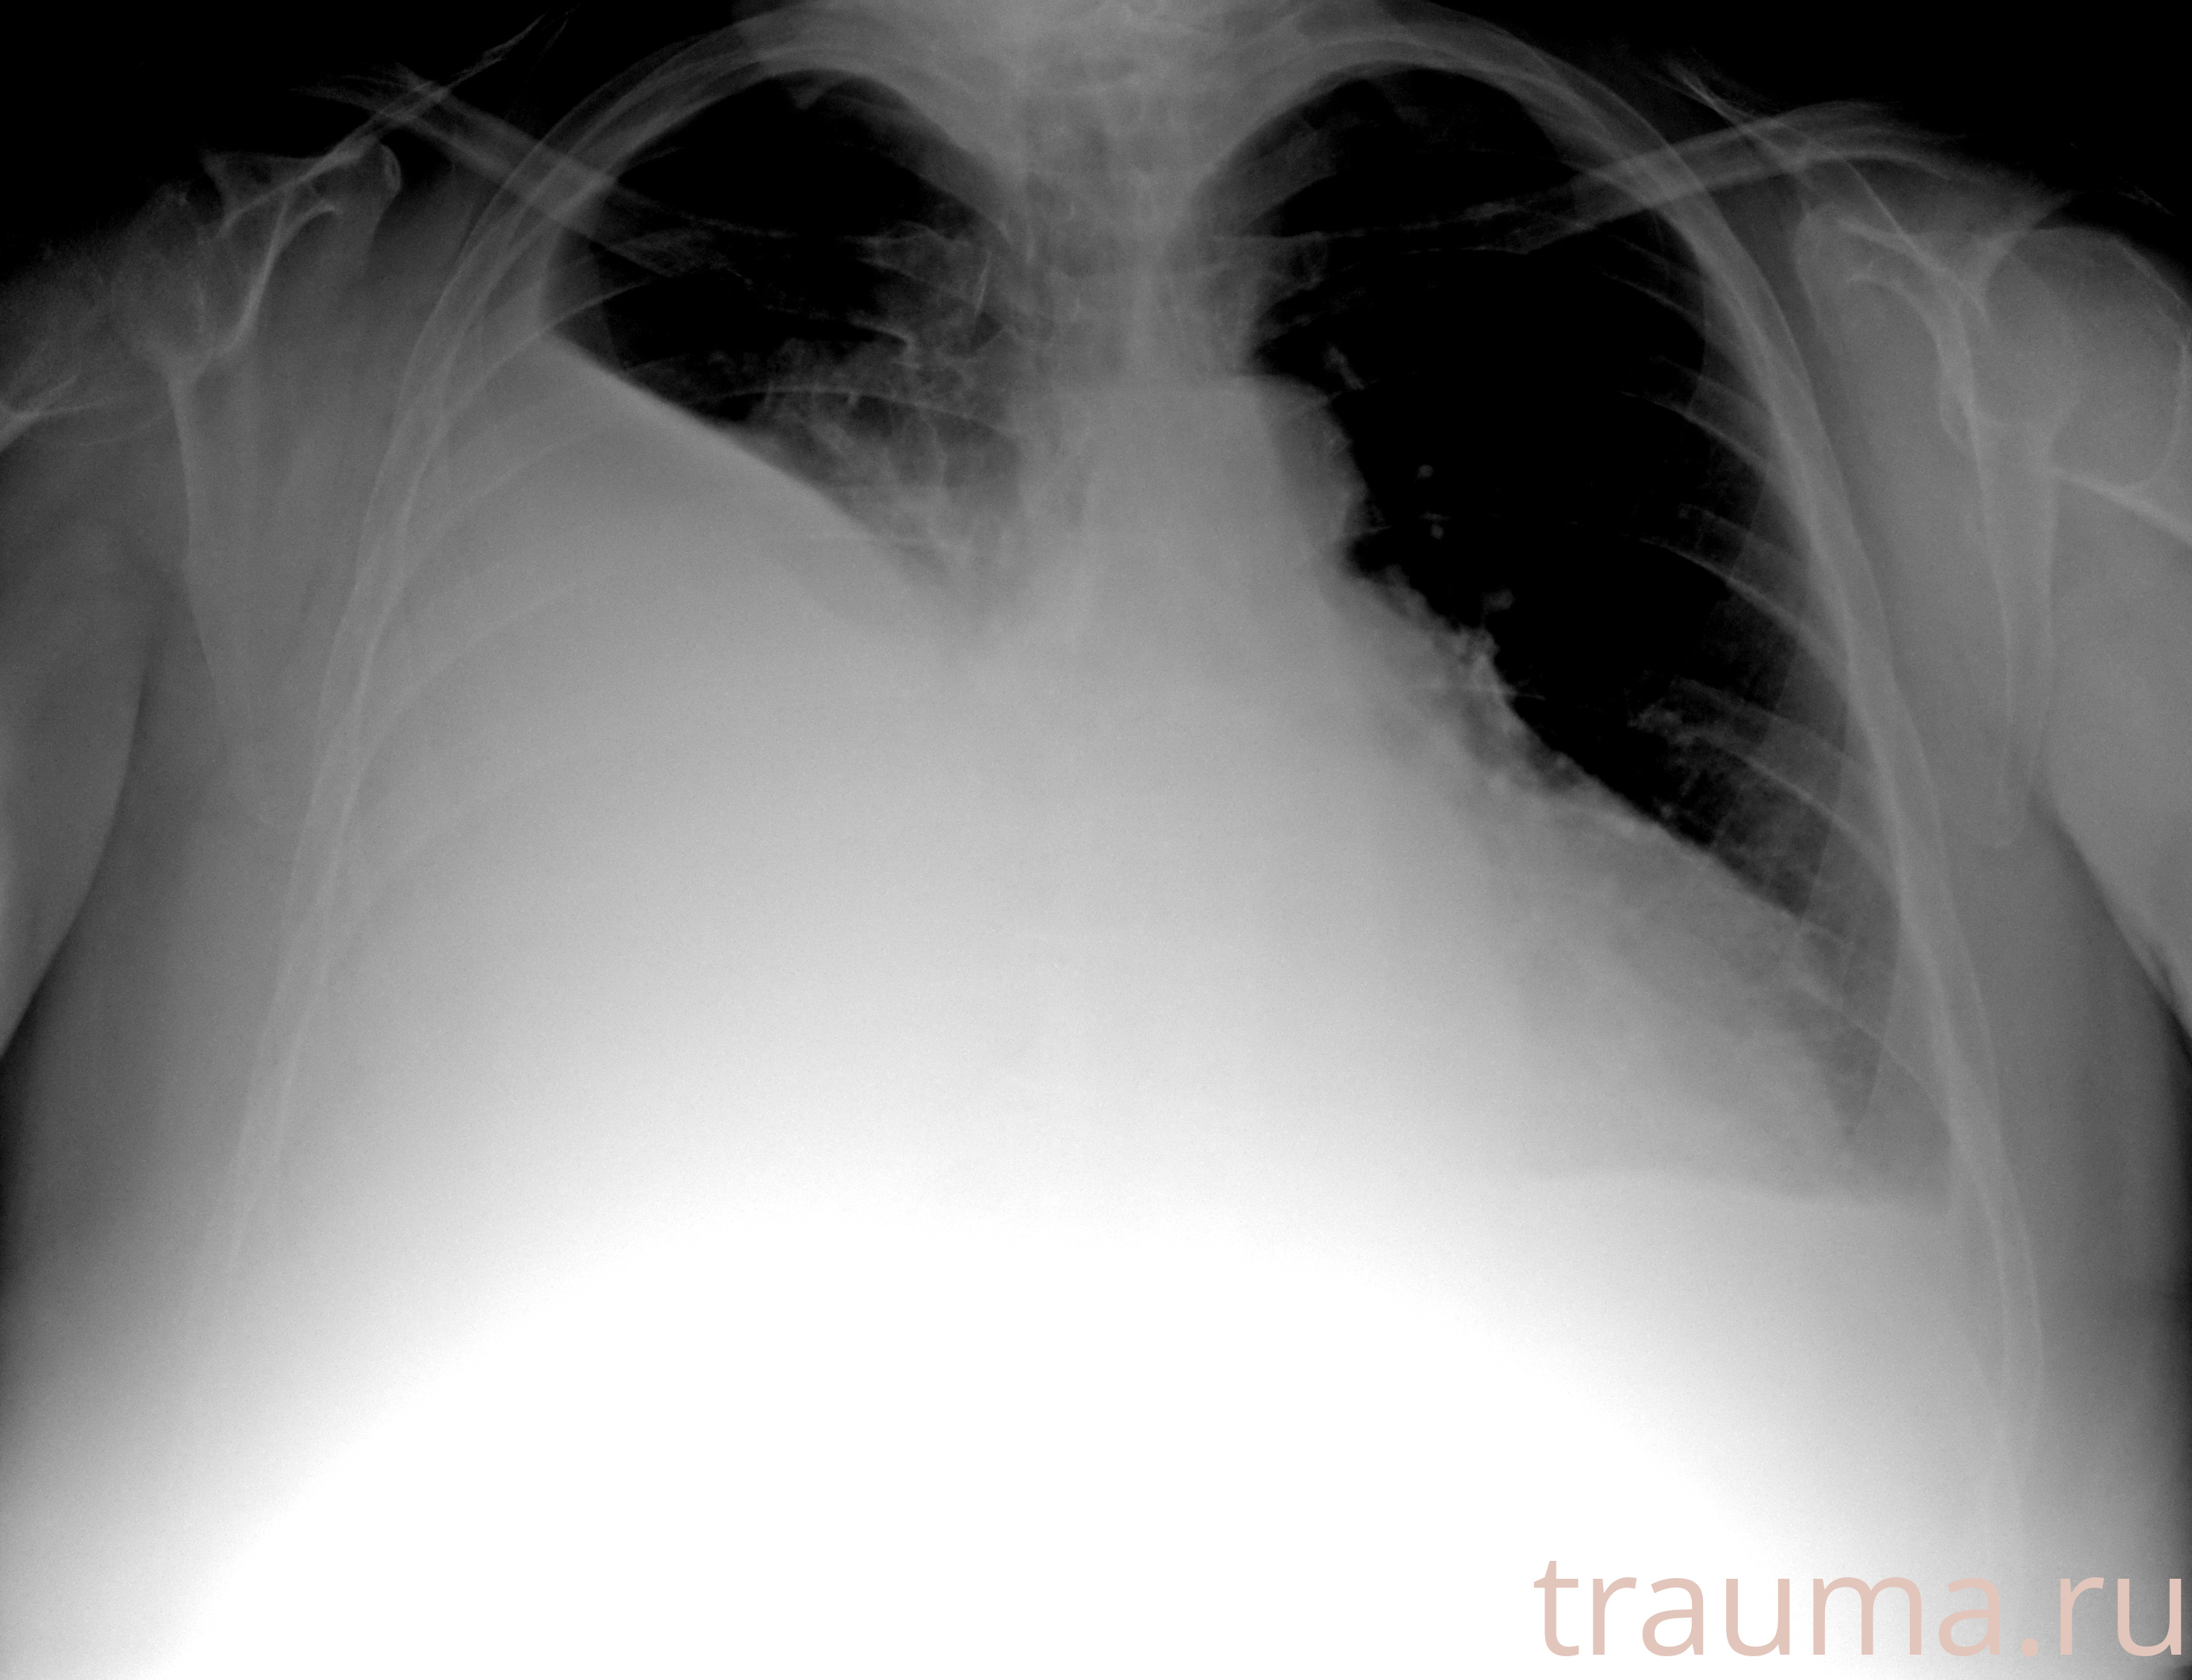

Рентген на дому: по вашему адресу приезжает врач-рентгенолог, травматолог-ортопед с мобильным рентгеновским аппаратом, проводит диагностику травмы или заболевания, делает необходимые рентгенограммы, дает рекомендации по дальнейшему лечению. Получить качественные снимки в домашних условиях возможно благодаря уникальной методике, разработанной МосРентген Центром для института  Склифосовского

при переломе шейки бедра и пневмонии от компании МосРентген Центр - партнера Института имени Склифосовского